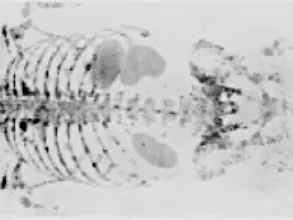

Basics of Whole-Body MRI in Oncology

This online 3-afternoon radiology course, facilitated by expert radiologist Prof. Giuseppe Petralia, covers key topics related to Whole-Body MRI Oncology.

This fellowship is designed for Radiologists, who want to learn the state of the art of the use of whole-body MRI in oncology . All aspects of whole-body MRI will be covered, from technical basis and MR protocols, to cancer specific clinical applications. Presentation of each topic will commence with a lecture followed by a review of carefully selected cases, to facilitate case-based learning.